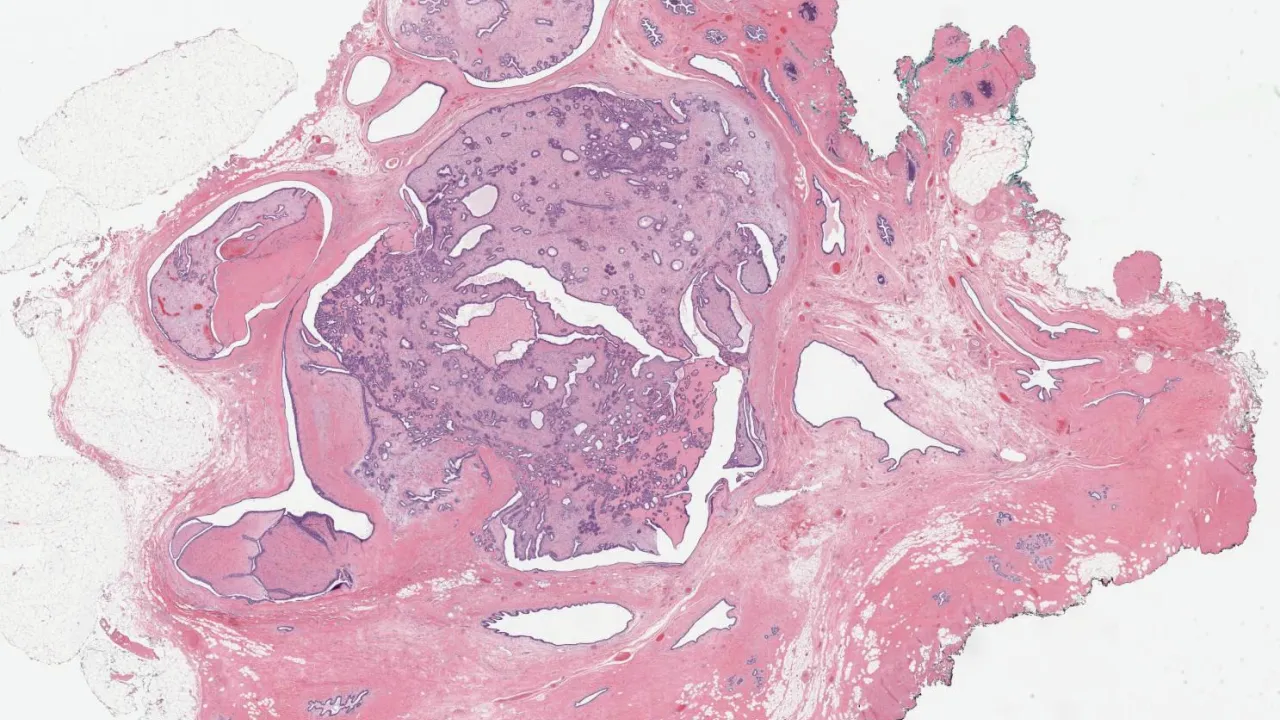

Sinus, Oncocytic Schneiderian papilloma